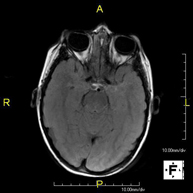

- Neuroradiology

- Brain MRI (cranial)

This non-invasive diagnostic procedure uses an electromagnetic field and radio waves (from a transmitter and receiver) to acquire high-definition anatomical images of the brain. It is a radiation-free procedure. Indicated for: vascular problems, memory loss, epilepsy, headache, malformations, suspected tumour, meningitis.